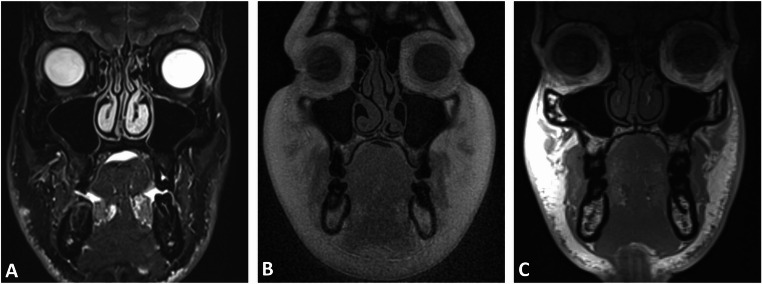

Methods: In this prospective study, healthy volunteers underwent 3T MRI using five protocols: DESS, SPACE STIR, SPACE SPAIR, T1-VIBE Dixon, and UTE. Eight trauma-prone regions, including the nasal septum, orbit, naso-orbito-ethmoidal (NOE) complex, zygomaticomaxillary complex, Le Fort regions, mandible, condyle, and dentoalveolar complex, were assessed. Image quality, artifacts, anatomical delineation, and bone-to-soft-tissue contrast were rated on a five-point Likert scale by three independent observers. Descriptive statistics and inter-rater agreement (intraclass correlation coefficients (ICCs)) were calculated.

Results: Sixteen participants (37.2 ± 12.9 years; 12 males, 4 females) were included, resulting in 80 MRI volumes and 640 regions for evaluation. UTE and VIBE-DIXON sequences achieved the highest ratings for image quality, artifact susceptibility, and anatomical delineation across most fracture-prone regions (ICC: 0.793-1; all p < 0.001). UTE excelled in visualizing NOE and Le Fort regions, while VIBE-DIXON performed best in mandibular and orbital imaging. Bone-to-soft-tissue contrast was highest in UTE and VIBE-DIXON, highlighting their diagnostic potential in simultaneous soft and hard tissue imaging. Inter-rater agreement was consistently high (ICC: 0.772-0.976; all p < 0.001).